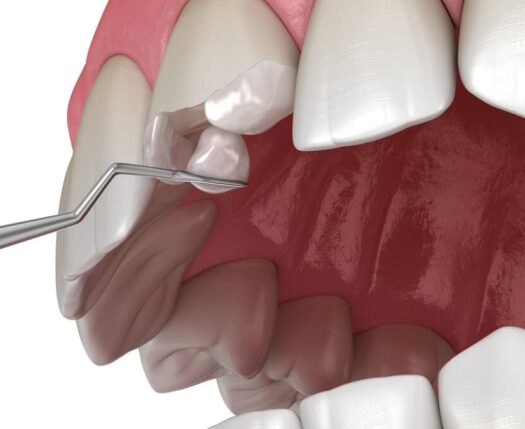

As facetas de porcelana são lâminas finas feitas de porcelana que são colocadas na parte frontal dos dentes para melhorar sua aparência. Já as restaurações de resina composta são feitas de um material compósito de resina que é moldado e esculpido diretamente nos dentes. Ambos os materiais têm suas próprias características e benefícios.

O processo de colocação de uma restauração estética varia dependendo do tipo de restauração escolhida. Geralmente, envolve a preparação do dente, a moldagem ou escaneamento digital dos dentes, a fabricação personalizada da restauração em um laboratório ou no consultório e, por fim, a cimentação ou colagem da restauração no dente.

Alguns tipos de restaurações estéticas, como as facetas de porcelana, envolvem o desgaste do esmalte dental e são consideradas irreversíveis, ou seja, os dentes precisam ser preparados para receber a restauração. No entanto, restaurações de resina composta podem ser removidas ou substituídas.